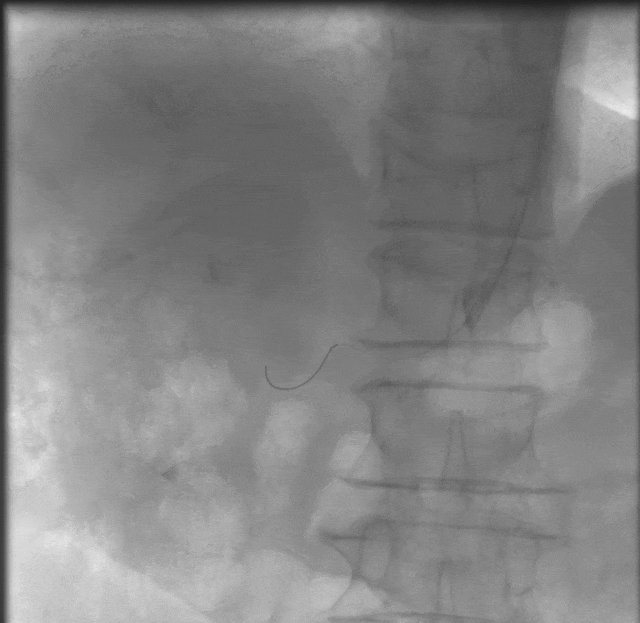

4.导丝支撑下交换引入CWB60605L-18震波球囊扩张右肾动脉狭窄段,完毕后复查造影示右肾动脉通畅,血管残余狭窄<20%,扩张效果满意,术毕。

患者血压较术前明显改善,小于130mmHg。